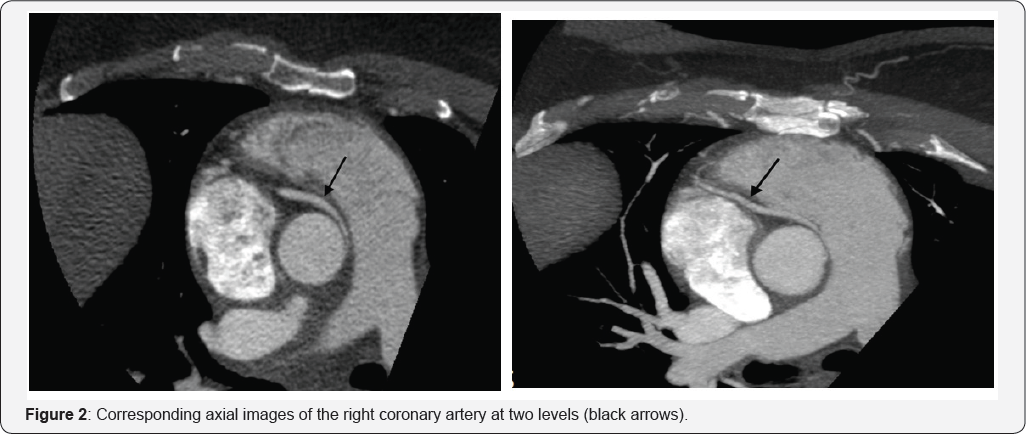

A 59-year-old woman with a history of hypertension and mild asthma was brought to the emergency department complaining of acute onset chest pain. Electrocardiogram en-route by EMS showed ST-segment elevations in inferior leads, which normalized on arrival to the emergency department thirty minutes later. Initial serum troponin-T was 0.12ng/ml (reference range: 0.0-0.1ng/ml). Coronary angiography revealed a suspected culprit, apical "wraparound" distal LAD stenosis with vasospasm and a difficult to engage right coronary artery (RCA) with 40% ostial stenosis. Her symptoms improved with intravenous nitroglycerin. Coronary computed tomography angiography showed an anomalous RCA arising from a separate origin in the left sinus of valsalva, with an "intramural" (within the wall of the aorta) and "inter-arterial" course (between the aorta and pulmonary artery) (Figure 1 & 2). Given that the patient's EKG findings and presentation could also have been due to RCA compression and that the inter-arterial course of an anomylous RCA has historically been associated with a poor prognosis (even sudden cardiac death), she was referred for surgery [1,2]. The patient did well with a single vessel bypass of the RCA with a saphenous vein graft without recurrent chest symptoms.